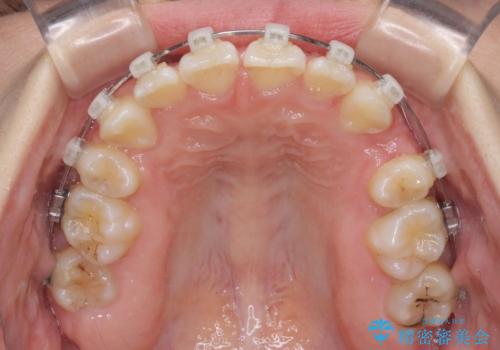

重度叢生と埋もれた奥歯 8本を抜歯したワイヤー矯正

- 内側に生えている歯や埋もれた奥歯を気にして来院された患者様です。

顎の骨が小さいため、歯列が収まりきらずに叢生や未萌出となっている状態でした。

埋もれた奥歯を萌出させ、さらにデコボコを解消するために、上下左右の第1小臼歯4本に加え、親知らず4本も抜歯し、ワイヤー装置にて矯正治療を行うこととしました。

親知らずの抜歯により埋もれた奥歯周辺の歯肉が切除され、矯正装置が装着できるようになりました。